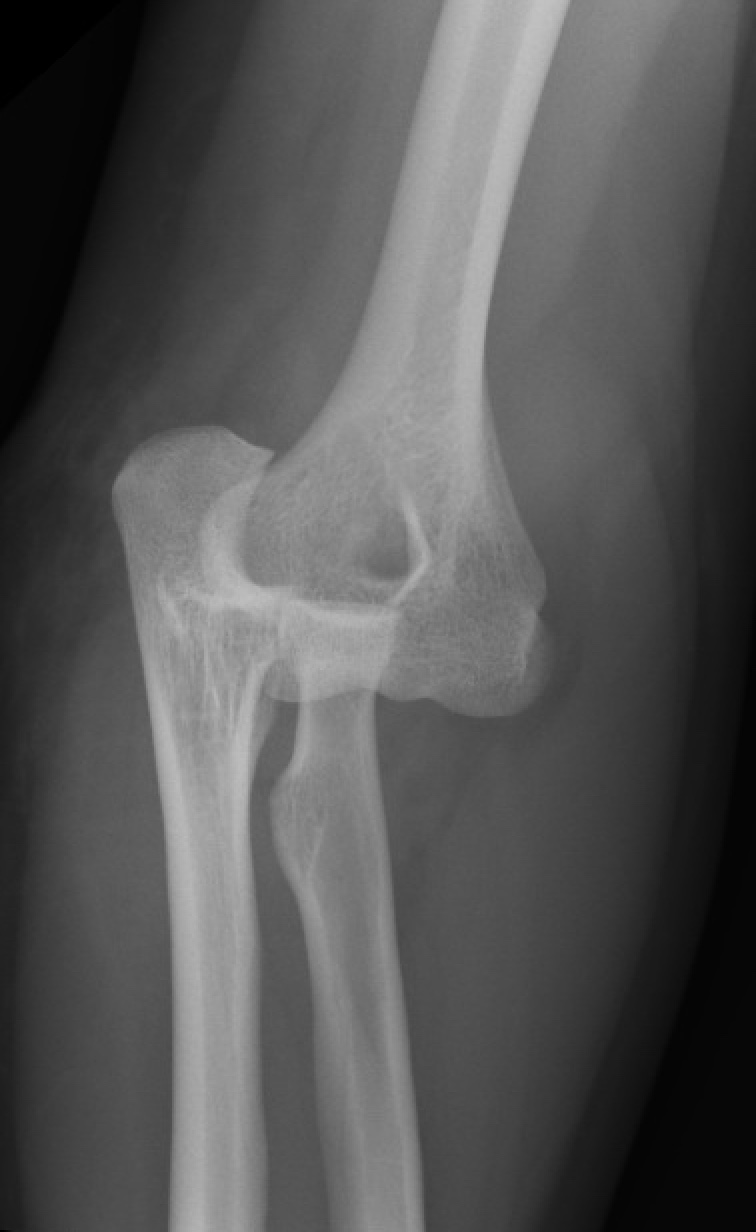

https://upload.orthobullets.com/topic/1018/images/posterolateralelbowdislocation.jpg

https://upload.orthobullets.com/topic/1018/images/posteriorelbowdislocation.jpg

https://upload.orthobullets.com/topic/1018/images/apterribletriad.jpg

• Elbow Dislocations are common elbow injuries which can be characterized as simple or complex depending on associated injury to nearby structures.

• Diagnosis can be made with plain radiographs. CT studies can be helpful to evaluate for loose bodies or for surgical planning.

• posterolateral is the most common type of dislocation (80%)

• based on anatomic location of olecranon relative to humerus

• posterolateral

• most common

• posteromedial